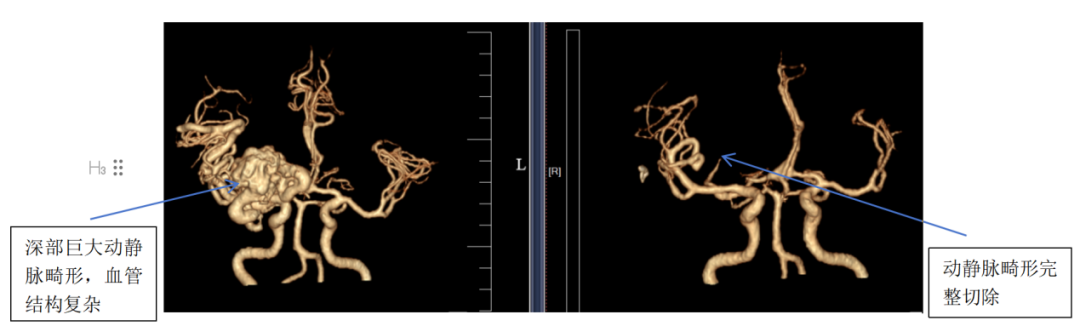

(图A:CTA血管造影检查)

术后复查CTA显示畸形血管全部切除,复查DSA显示血流恢复正常,重要血管结构均完整保留。经康复观察,患者无任何并发症,头痛与癫痫消失,精神与记忆恢复正常。

CTA血管造影检查:可以静态显示血管,如图A;

DSA全脑血管造影:比CTA更精确,且可以动态显示血流,确诊“金标准”,如图B。